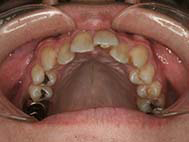

エンジェルクラウン e-max・セラミッククラウン 症例クイック矯正

東淀川 矯正歯科 インビザライン抜歯症例 インプラント矯正 口腔外科 親知らず抜歯早い はしもと歯科クリニック矯正歯科